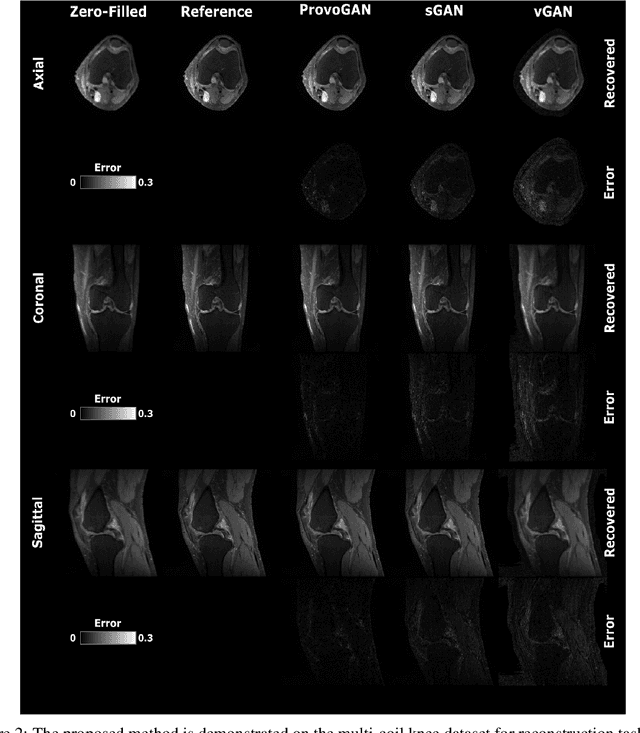

Abstract:Magnetic resonance imaging (MRI) offers the flexibility to image a given anatomic volume under a multitude of tissue contrasts. Yet, scan time considerations put stringent limits on the quality and diversity of MRI data. The gold-standard approach to alleviate this limitation is to recover high-quality images from data undersampled across various dimensions such as the Fourier domain or contrast sets. A central divide among recovery methods is whether the anatomy is processed per volume or per cross-section. Volumetric models offer enhanced capture of global contextual information, but they can suffer from suboptimal learning due to elevated model complexity. Cross-sectional models with lower complexity offer improved learning behavior, yet they ignore contextual information across the longitudinal dimension of the volume. Here, we introduce a novel data-efficient progressively volumetrized generative model (ProvoGAN) that decomposes complex volumetric image recovery tasks into a series of simpler cross-sectional tasks across individual rectilinear dimensions. ProvoGAN effectively captures global context and recovers fine-structural details across all dimensions, while maintaining low model complexity and data-efficiency advantages of cross-sectional models. Comprehensive demonstrations on mainstream MRI reconstruction and synthesis tasks show that ProvoGAN yields superior performance to state-of-the-art volumetric and cross-sectional models.